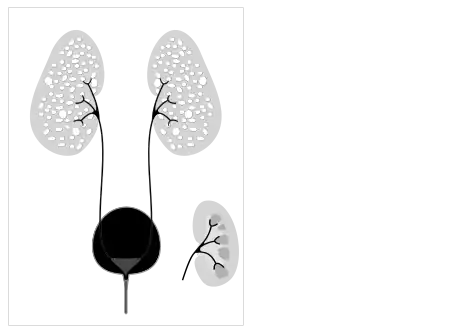

- Illustration-Autosomal recessive polycystic kidney disease with a normal kidney inset